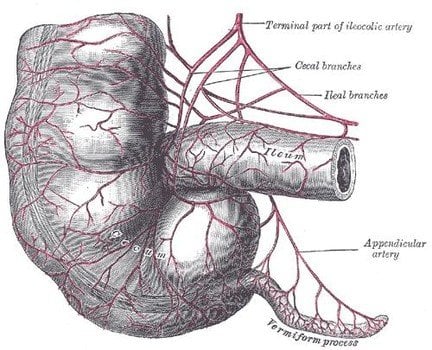

9. The Appendix

The most famous example of a vestigial organ is the Appendix, which is so useless that it often has to be removed from the body if it becomes infected. Once upon a time, it might have been useful in processing the cellulose from our green diet. As our preference of veggies declined, however, the appendix became less important. What’s more interesting is the fact that natural selection prefers large organs, as they are less likely to get infected. This means that the appendix is probably going to be a part of our anatomy longer than our little toe, which is just about as useless. The latest theory regarding the appendix is that it’s believed to be a repository for beneficial bacteria.